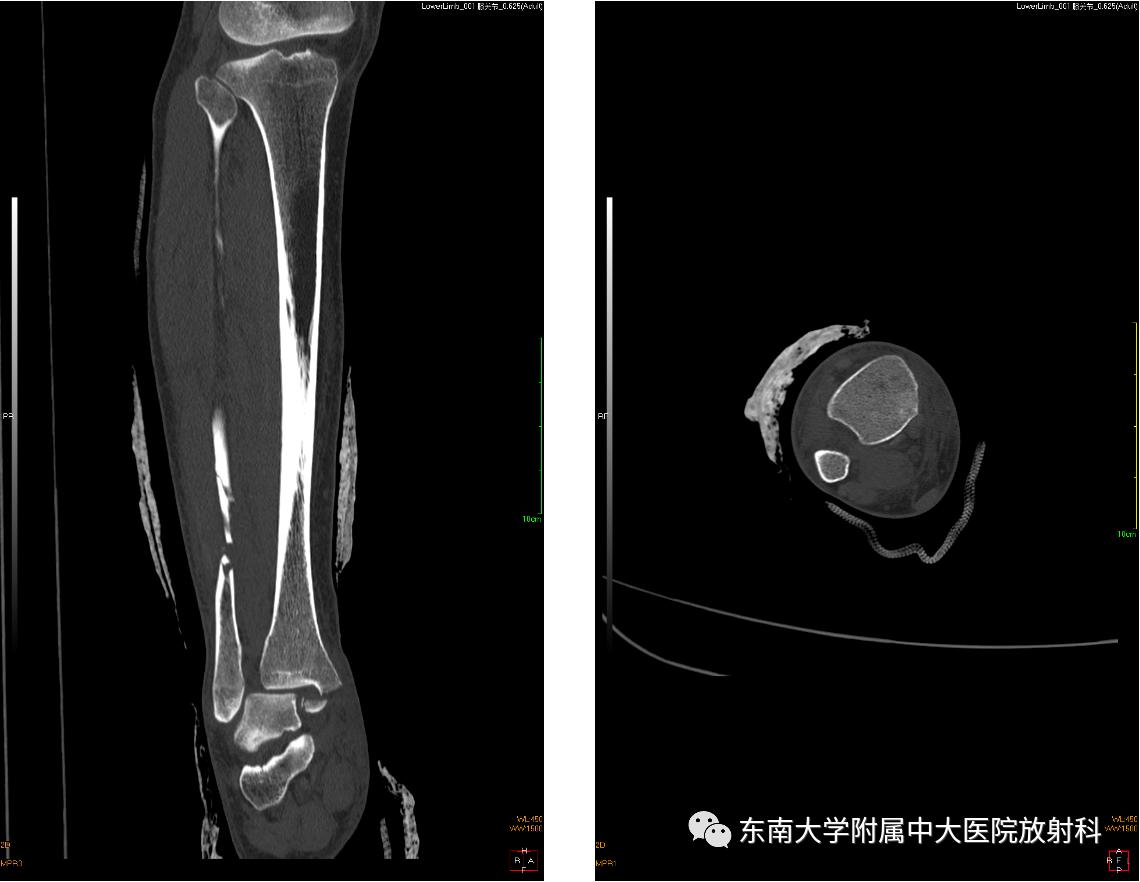

影像学表现

左腓骨下段骨折伴下胫腓联合分离,好文分享深度揭秘